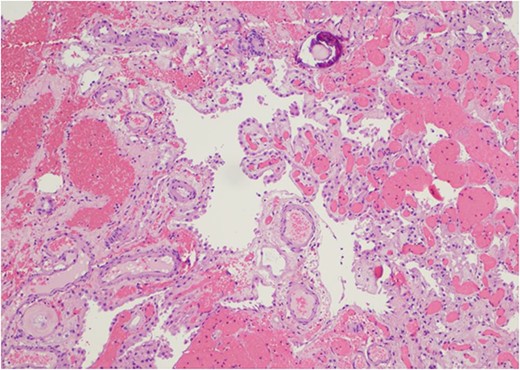

Only one small piece of the cystic lesion was obtained and entirely submitted for touch preparation and frozen section (Fig. 2), which demonstrated a hypercellular lesion composed of uniform ovoid cells with salt-and-pepper chromatin, lacking pleomorphism, grooves, nucleoli, increased mitotic activity, and had no papillary architecture. The intraventricular lesion was submitted separately and had the morphology of a benign papilloma (Fig. 3), staining with cytokeratin AE1/AE3, with no staining with GFAP. Because of the histological discrepancy of the first and second specimens, and the limited amount of tissue from the cystic lesion, the paraffin embedded tissue of the cystic lesion was submitted for methylation profiling by NIH. The methylation profiling had a maximum score of 1 for both class and subclass for EVN, WHO grade 2 (Fig. 4).

(a) and (b) The touch preparation and frozen section control shows similar histologic features. The cystic lesion shows a moderately hypercellular tumor, with uniform round nuclei, irregular distribution of chromatin, and a moderate amount of eosinophilic cytoplasm. There is no distinct fibrillary background (Hematoxylin and eosin, 400×).